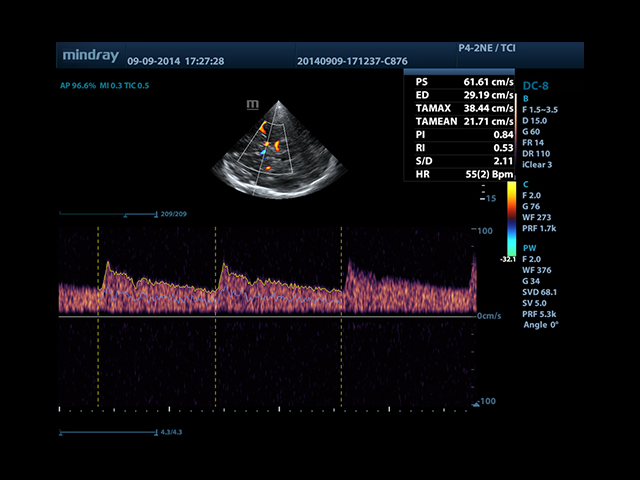

Mindray DC-8 Exp оснащен новым поколением датчиков с увеличенным количеством элементов и инновационной технологией "3T". Это позволяет достичь высокой детализации и качества изображения. Благодаря новейшей технологии iFlow, можно визуализировать даже самые мелкие сосуды и кровеносные пути.

Сверхширокополосная нелинейная обработка изображений снижает визуальные шумы на 30% по сравнению с другими системами. Технология iClear позволяет устранить зернистость изображения, а iBeam (технология пространственного компаундинга) обеспечивает высокое качество сканирования органов и тканей под различными углами.

• Импульсный допплер и HPRF

• Режимы сканирования: B/M/CFM/PDI/Направленный PDI/PW/Цветной M-режим;

• Автоматическая трассировка допплеровского спектра с расчетом параметров и индексов

• Smart Doppler™ - автоматическая подстройка расположения рамки цветового допплера и контрольного объема импульсно-волнового допплера